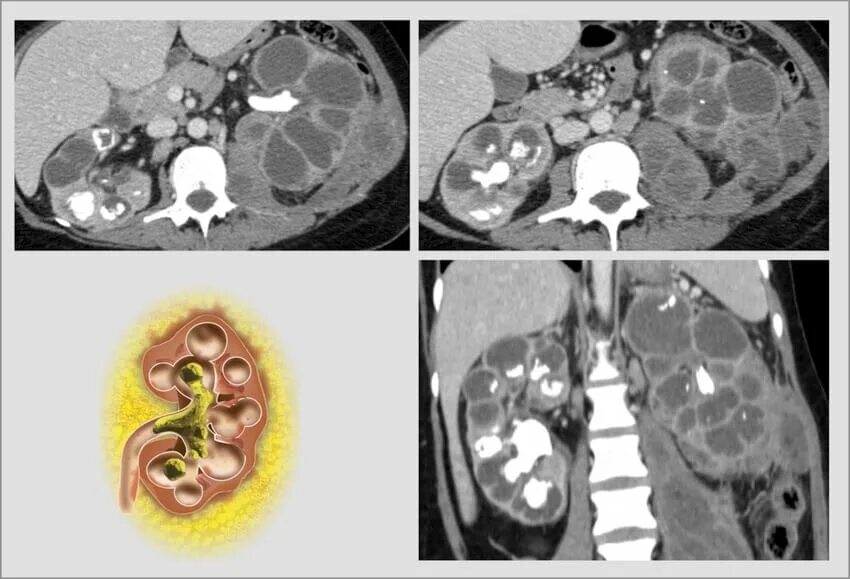

Пиелонефрит кт